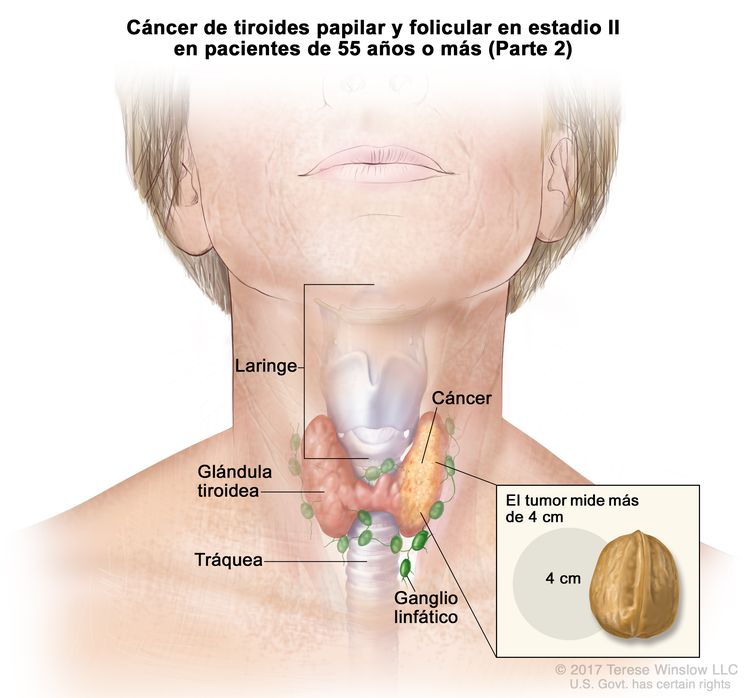

cancer papilar de tiroides El cáncer se origina cuando las células comienzan a crecer sin control. Cáncer de tiroides diferenciado (papilar o folicular) en pacientes menores de 55 años de edad las personas más jóvenes tienen menores probabilidades de morir a causa del. ¿qué es un carcinoma papilar de la tiroides? A nivel mundial, se estima que en 2020 se diagnosticó cáncer de tiroides a 586.202 personas. Most papillary thyroid cancers are small and respond well to treatment, even if the cancer cells spread to the lymph nodes in the neck. Hay cuatro tipos principales de cáncer de tiroides, los cuales presentan distinta malignidad. También puede llamarse cáncer de tiroides diferenciado. Me fui al anticanceroso de maracay, aragua, me hicieron un paaf y ahí salió el adenocarcinoma papilar tiroideo”, expresó caro.

Carcinoma papilar de tiroides